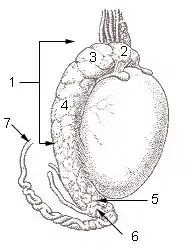

2: Cabeza del epidídimo

3: Lóbulos del epidídimo

4: Cuerpo del epidídimo

5: Cola del epidídimo

6: Conducto del epididimo

7: Conducto deferente.